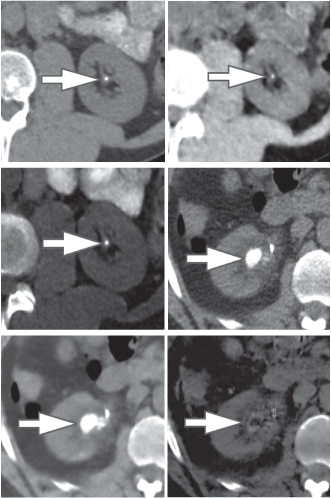

Conversely, non-uric acid stones demonstrate exaggerated attenuation at eighty kVp because Uric acids stones demonstrate exaggerated photons attenuation at a hundred and forty kVp as a result of the attenuation is driven primarily by Compton scatter (due to lighter 30% chemical composition). Conversely, non-uric acid stones demonstrate exaggerated attenuation at eighty kVp because of exaggerated electricity impact contribution from the heavier parts nearing the K-edge of the metallic element (Z=20). victimization the two-material (basis pair) decomposition approach on DECT, water and iodine image datasets square measure generated. Stone look on water image solely suggests acid calculi, whereas look on every water and iodine image indicate non-uric acid stones (Figure 2). Effective Z (Zeff) pictures square measure AN alternate approach for characterizing internal organ calculi and should be achieved in the offline computing device. Zeff weighs each the attenuation and number of bound materials, thereby serving to in characteristic the materials that are predominant among mixed stones.

Figure 2. 45-year-old man (top row) and 60-year-old man (bottom row) with renal lithiasis. typical true unenhanced image (A), water material decomposition image (B), and iodine material decomposition image (C) demonstrate a non-uric acid stone, that's hyperdense on every water and iodine pictures (arrows) in single offer DECT (GE). at intervals, the second patient, typical true unenhanced image (D), water image (E), and iodine image (F) demonstrate a mixed stone that is predominantly acid in composition (arrows). The stone is not hyperdense on iodine pictures aside from its peripheral rim (F). Our experience has shown that acid stones typically demonstrate a rim of Ca deposition.